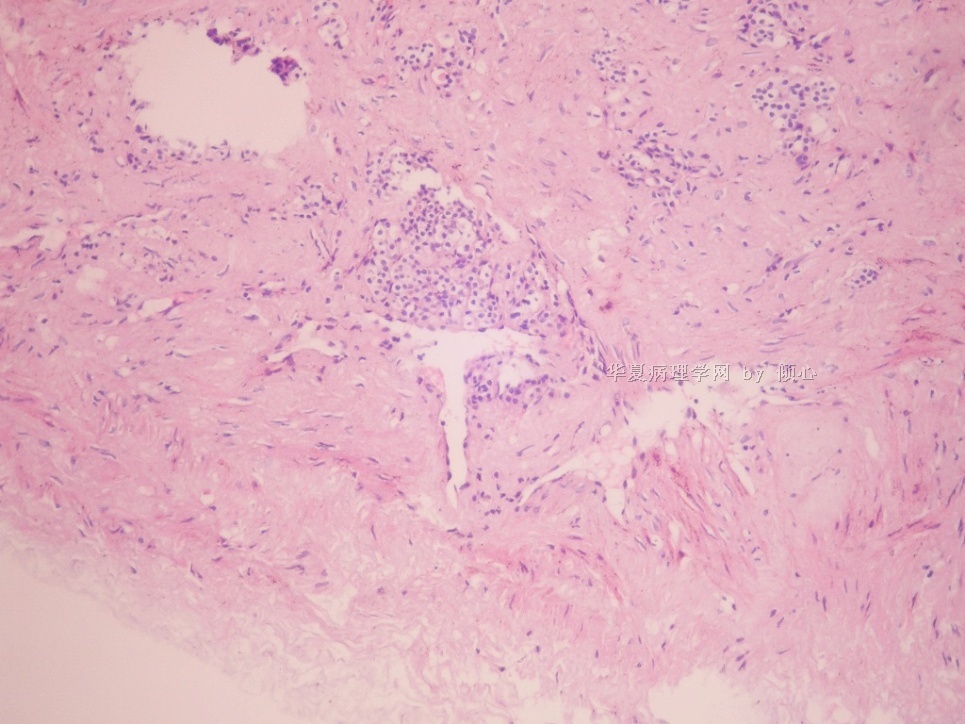

姓    名: ××× 性别:  女 年龄:  41岁

标本名称:  肾微创手术标本,囊壁样组织

简要病史:  体检发现左肾囊肿

肉眼检查:  囊壁样物  5*3*0.2cm一堆,囊壁后0.1cm囊壁粉白色,内容未见,未见明显实性区。

手术所见:在左肾上极内上方见囊肿,大小约7.0×7.0cm,游离囊肿,表面筋膜及脂肪组织,切开囊肿,吸出囊液,囊液无色透明,以超声刀沿正常肾皮质边缘切除囊壁(术式:经后腹膜腔途径,腹腔镜下左肾囊肿去顶减压术)。

本帖最后由 于 2010-05-26 20:13:00 编辑  在左肾上极内见囊肿 ,这些透亮细胞在囊壁内。

可是,这是比较典型的肾上腺皮质细胞,不大像肾透明细胞癌的细胞。与之鉴别还是有必要的。需做IHC标记。

IHC广谱CK阳性,vimentin,RCC,CD10,CD68均阴性。

以下的图像是CK,取下的组织并不多,很少量的透亮细胞位于纤维性的囊壁内。需要鉴别的是残留的肾小管和囊性肾细胞癌。

囊壁无被覆透明细胞,纤维内的细胞巢有基底膜样物围绕,vimentin阴性,提示为萎缩的肾小管。冰冻时除非见到明显的被覆透明细胞,反之则请泌尿医师等石蜡。